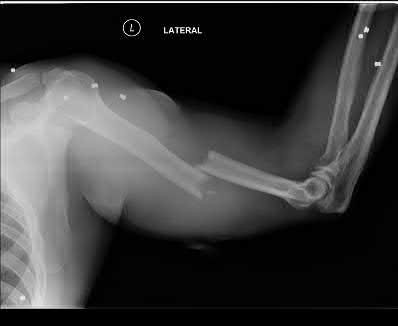

A 34-year-old male falls from a roof and sustains a right elbow dislocation that is closed reduced in the emergency room. An AP radiograph is shown in Figure A. This injury pattern is at highest risk for which of the following?

Anteromedial coronoid facet fracture and LCL injury following an elbow dislocation is commonly associated with varus posteromedial rotatory instability. Varus and posteromedial rotation force on the forearm results in rupture of the LCL from its humeral origin. As the LCL ruptures, the medial coronoid process is fractured as it impacts against and under the medial trochlea. Fracture involvement of the sublime tubercle, where the MCL attaches, can lead to more instability. Ulnar neuropathy can be seen following this injury pattern but AIN and PIN nerve palsy do not commonly characterize this injury pattern.

The review article by O'Driscoll highlights key points in diagnosis and management of capitellum, distal humerus, coronoid, and terrible triad injuries.

The article by Doornberg and Ring is a Level 4 study of 18 patients that sustained varus posteromedial rotational injuries resulting in anteromedial facet coronoid fractures. They found that lack of fixation at injury or malunion of the anteromedial facet were significant predictors of suboptimal functional outcome and development of arthrosis.

The anteromedial facet is highlighted in yellow as displayed in Illustration A. Illustration B depicts the lateral collateral ligament injury also evident during

varus stress fluroscopic examination, due to tension failure of the LCL off its humeral origin during the various mechanism.